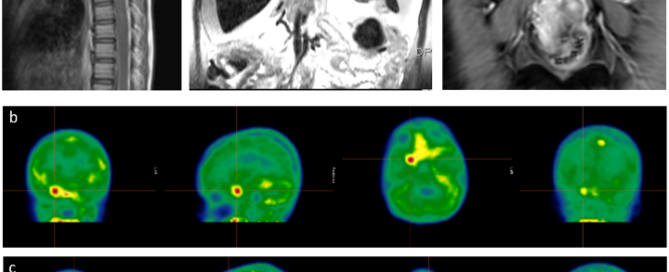

免疫疗法对表皮生长因子受体 (EGFR) 突变的非小细胞肺癌 (NSCLC) 患者效果较差,其肿瘤微环境的特征尚不明确。 研究者使用单细胞转录组测序和多重荧光免疫组化技术(mIHC)研究了EGFR突变型和EGFR野生型肺腺癌的免疫微环境差异,发现EGFR突变患者的肿瘤细胞与免疫治疗无效样本有相似特征,而EGFR野生型患者的肿瘤细胞与免疫治疗有效样本的特征更为接近。相较于EGFR野生型患者,EGFR突变患者的CD8+组织驻留记忆细胞数量,与B细胞趋化有关的CXCL13表达水平,以及PD-1、PD-L1多种免疫检查点分子的表达显著降低,意味着EGFR突变患者无法有效形成三级淋巴结构,可能是EGFR突变患者对免疫疗法响应度低下的原因。 该研究提供了对单细胞水平EGFR突变型肺腺癌免疫景观的全面了解,缺乏CD8+TRM可能是导致EGFR突变型肺腺癌抑制性免疫微环境的关键因素。 目前,阔然基因已经布局了整套多重荧光免疫组化技术(mIHC)平台,包括Kreep染色试剂盒、KR-HT5高通量荧光病理切片扫描系统和KRIAS医学病理影像分析软件,并开发了6款检测产品。 三大技术突破 依托多重荧光免疫组化技术平台,阔然基因推出了肿瘤免疫微环境全景分析解决方案,全景剖析肿瘤免疫微环境中的杀伤性T细胞、耗竭性T细胞、巨噬细胞、B细胞、三级淋巴结构和免疫检查点受体的浸润情况,全面评估患者的预后和接受免疫抑制剂治疗的疗效,挖掘肿瘤免疫微环境与肿瘤发生发展、复发、转移和耐药机制的关系和临床分子机理。 参考文献: J Immunother Cancer.2022 Jan;10(2):e003534.